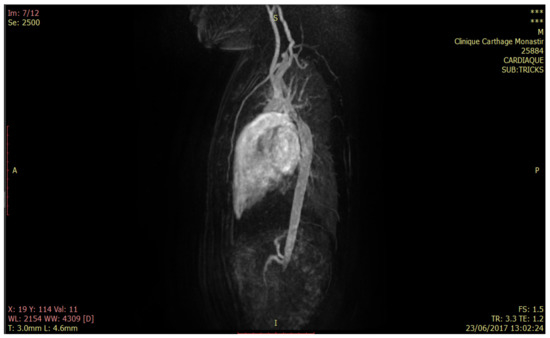

6.1. Model of the Geometry of the Descending Aorta in 3D

In this section, we proceed to the first phase of our 5D model, which consists of defining the geometry of the descending aorta in 3D. This step states the reconstruction of the aortic model from the TRICKS sections, as shown in Figure 5.

Figure 5.

Sample of TRICKS cuts for 2500 s of acquisition.